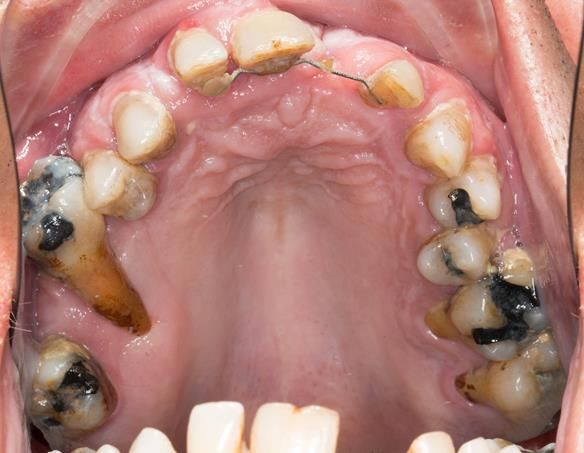

- Generalised periodontitis; stage IV grade C: currently unstable, risk factors: smoker.

- The remaining maxillary teeth had hopeless prognosis in the short term. They exhibited 80 - 100% alveolar bone loss with increased mobility (Grade 2 - 3).

- Extraction of all upper teeth and LR5 and LL4 and fitting of immediate acrylic based (Mk 1) dentures - complete upper and lower partial

The clinical situation and treatment process is shown in detail below with photographs.